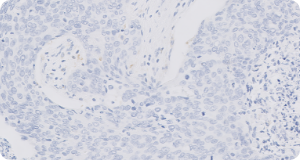

CCECC = carcinoma de células escamosas de cabeza y cuello; CPS = combined positive score.;

Referencia: 1. Manual de interpretación de Agilent Technologies, Inc. PD-L1 IHC 22C3 pharmDx: carcinoma de células escamosas de cabeza y cuello (CCECC).